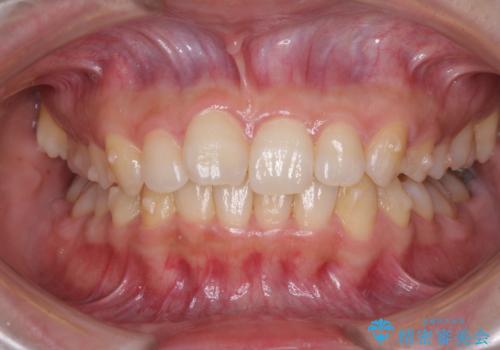

最難関と思われたシザーズバイトは比較的短期間で解消されました。

しかし、治療中に2度の出産を経験され、治療期間は長くなってしまいましたが、咬みやすく、清掃しやすい歯列を獲得することができました。